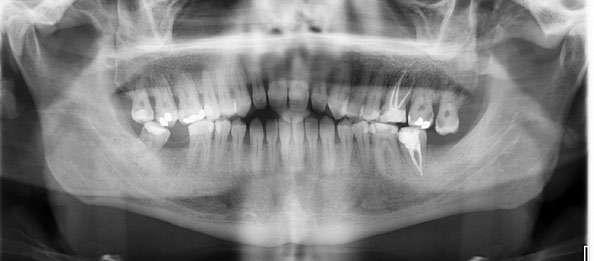

3. Análisis radiográfico y tomográfico (Ilustración 4):

 Constricción maxilar con deficiencia transversal

> 5 mm.

 Clase III esquelética.

 Patrón esquelético hiperdivergente con el plano oclusal mandibular compensado con rotación anti-horaria.

 Sutura palatina media parcialmente osificada (8) (9).

 Posición de terceros molares no favorable, por lo que se recomendó extracción.

Ilustración 4. Registros radiográficos iniciales de estudio.